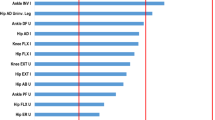

Correlation of function, pain and muscle measures

Muscle bulk correlated negatively with pain scores such that greater muscle bulk was associated with lower pain scores (Table 3). This association was significant for the quadriceps and hip adductors but did not reach significance in other muscle groups. Quadriceps thickness was strongly correlated with function, with greater thickness associated with better function. Other muscle groups showed mild to moderate correlation with function, with significance seen in the symptomatic hip adductors. Symptomatic joint stiffness was not found to correlate with any measured muscle thickness. Age and symptom duration were not correlated with muscle thickness in any muscle groups. Males showed higher values for muscle thickness than females for all muscle groups.

Similar to ultrasound-measured bulk, muscle torque generated by all muscle groups was negatively correlated with pain such that lower muscle torque was correlated with worse pain (Table 3). This correlation reached levels of significance for hip abductors, hip adductors, and plantarflexors on both limbs. Importantly, there was no significant correlation found between pain and quadriceps torque. Analyzing correlation with function, muscle torques were negatively correlated with function, with significant correlation seen in the hip abductors, adductors, and plantarflexors, but not quadriceps.